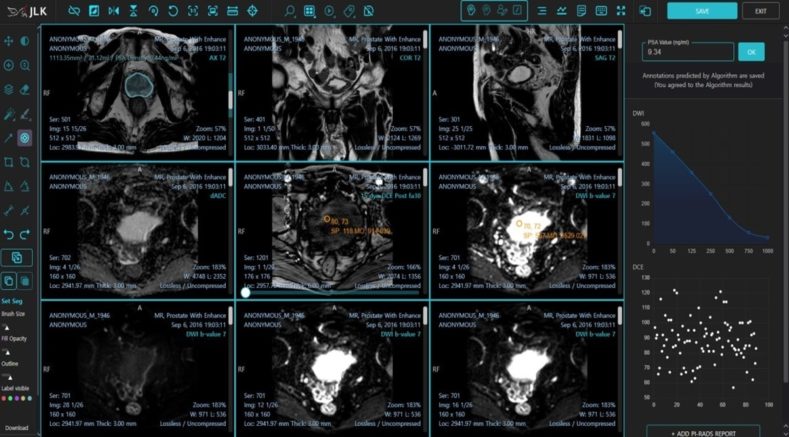

이번 FDA에서 승인된 MEDIHUB Prostate는 제이엘케이가 서울아산병원, 미국 미주리 대학과의 임상시험으로 개발한 전립선암진단 AI 솔루션이다. 전립선암의 진단과 추적에는 다중 매개변수(Multiparametric) 전립선 MR 영상이 활용되며, 질병에 대한 조직학적 이해 및 MR 영상에 대한 많은 경험이 필요하다.

또한 판독의사들의 숙련도에 따라 진단의 난이도가 있는 질환으로 세계적으로 인증된 바이오 마커인 PIRADS (Prostate Imaging Reporting and Data System) 점수를 표준화해 사용하고 있다.

MEDIHUB Prostate는 인공지능을 활용해 Multiparametric 전립선 MR 영상을 복합적으로 분석하고 AI가 PIRADS 진단 및 PSA(전립선 특이 항원, Prostate-Specific Antigen) density 진단 등의 전립선암 진단에 필요한 모든 데이터를 제공한다. 전립선암 분야의 핵심 기업은 Abbott, Siemens, Genomic Health, Roche, Bayer, MDx Health 등이 있다.